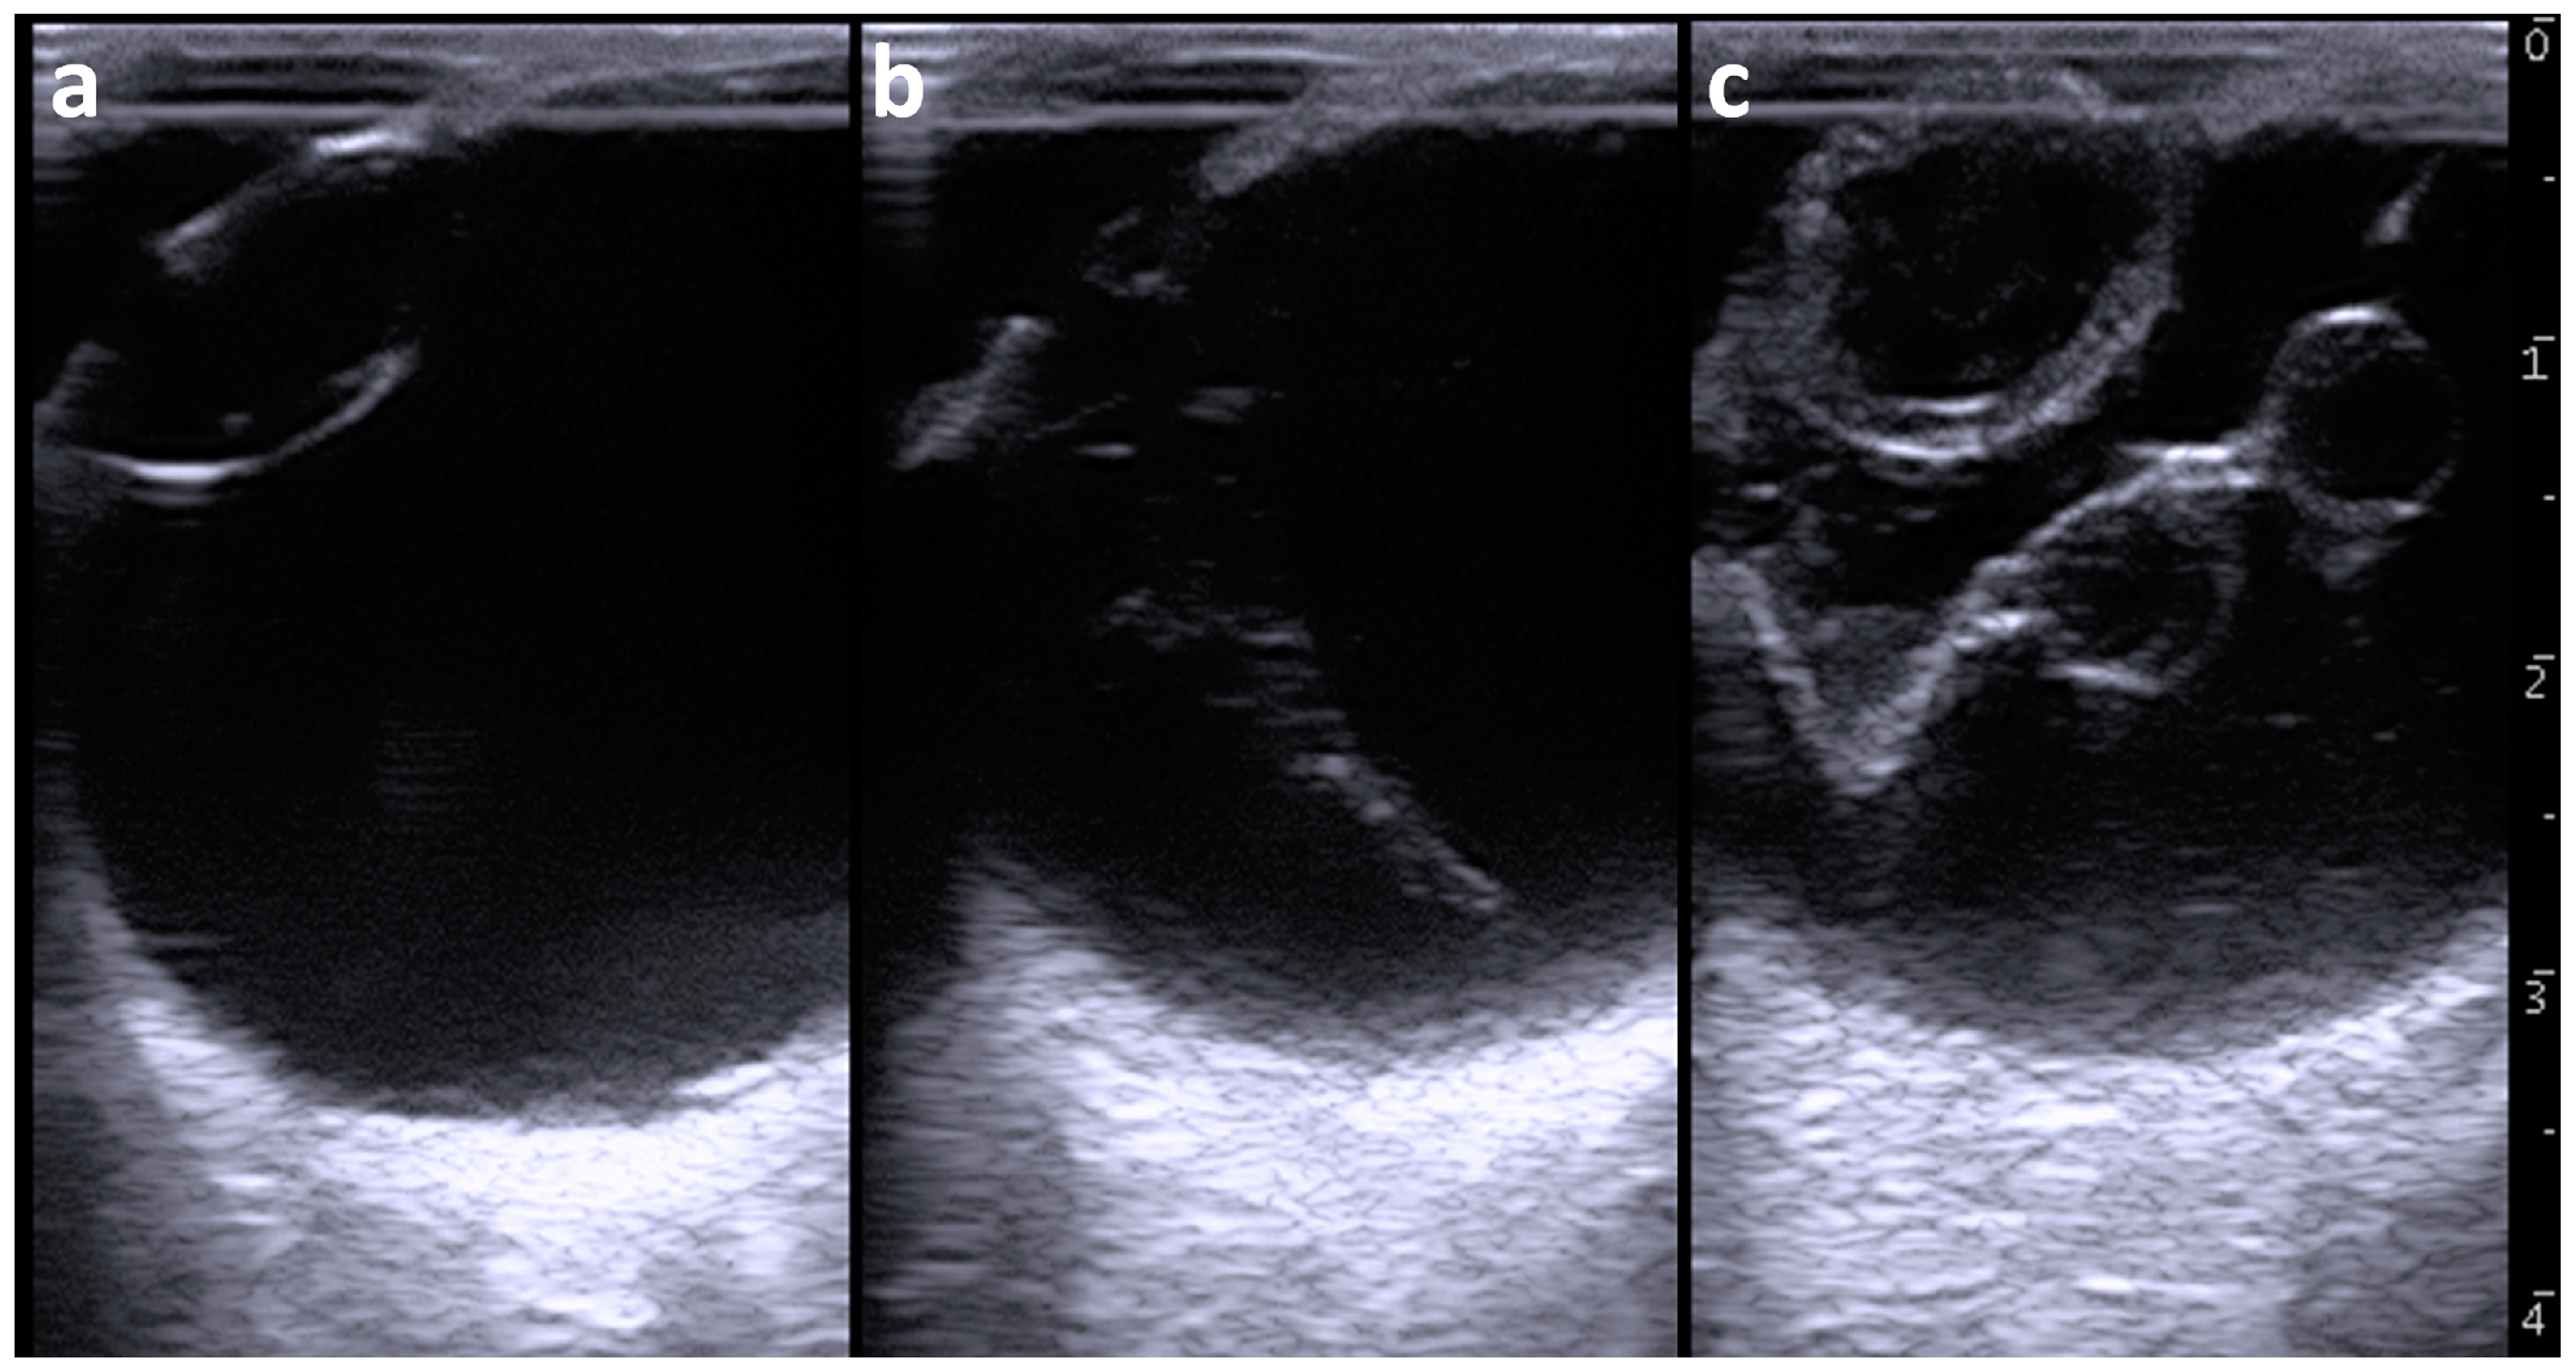

Figure 2.

Ultrasonographic appearances of the left eyeball (a,b) and right eyeball (c). (a) The lens is anechoic and surrounded by echogenic lines of the anterior and posterior lens capsules within the left eyeball. (b) The corn-like structure is heterogeneously echogenic and present between the posterior lens capsule and the deepest scleroretinal rim within the vitreous body of the left eyeball. (c) A V-shaped membranous structure is present and accompanied by two cystic structures within the vitreous body of the right eyeball. The enlarged lens is heterogeneously anechoic to hypoechoic and is lined by the thickened and irregular anterior and posterior lens capsules. Scale = 10 mm.

Ultrasonography of the right eyeball revealed that the lens was lined by thickened and irregular anterior and posterior lens capsules (Figure 2c). The anterior lens capsule appeared as a heterogeneous and 3 to 4 mm thick structure and was slightly thicker compared with that of the posterior lens capsule (2 to 3 mm thickness). The posterior lens capsule appeared as a heterogeneous echogenic architecture lined by two hyperechoic anterior and posterior lines. The lens was heterogeneously seen with a mixture of anechoic and hypoechoic contents. The vitreous humor was heterogeneously anechoic and included hypoechoic contents. A V-shaped membranous structure could be seen within the vitreous body. The membranous structure was irregular and 1 to 3 mm thick. The tip of the V-shaped structure was located in the area of the optic disc, although it was unclear whether it ended within the optic disc. The two proximal edges of the V-shaped structure ended in the scleroretinal rim near the ciliary body. Two cystic structures were formed alongside each other in the center of one line of the V-shape of the membranous structure. The cystic structures were outlined by irregular and 1 to 2 mm thick echogenic lines and included heterogenous anechoic contents. The diameters of the two cystic lesions were 6.2 × 6.6 mm and 8.0 × 6.1 mm. No cystic lesion was evident in the other line of the V-shaped membranous structure.

Ocular ultrasonography was carried out using a portable-type ultrasound machine (MyLabOne VET, Esaote Co., Genoa, Italy). Prior to the examination, an ophthalmic local anesthetic (Benoxil ophthalmic solution 0.4%, Santen Pharmaceuticals Co., Ltd., Osaka, Japan) was topically applied for the surface of the cornea. A 10.0 MHz linear probe was applied to the surfaces of the cornea in the horizontal plane (medial to lateral direction) soon after topical use of an ultrasound gel, while the animal was kept in standing position without sedation. Ultrasonography of the left eyeball revealed that the anterior aqueous and vitreous humors were normally anechoic (Figure 2a). The anechoic lens was surrounded by echogenic lines of the anterior and posterior lens capsules. A corn-like echogenic structure appeared between the posterior lens capsule and the deepest scleroretinal rim within the vitreous body when the probe was slightly moved medially from the center (Figure 2b). It was unclear whether the proximal region of this structure had adhered to the posterior lens capsule. The widest proximal region of the corn-like echogenic structure was approximately 1 cm thick. The distal region of this structure adhered to the deepest scleroretinal rim (possibly corresponding to the optic disc) and was thinnest at 2 to 3 mm thickness. A persistent hyaloid artery was suspected based on this ultrasonographic finding.

On the ultrasonogram of bovine eyes, the intraocular structures can be clearly identified by the different echogenicity of each structure; the cornea, the anterior and posterior lens capsules, and the scleroretinal rim appear hyperechoic; and the aqueous humors, the lens, and the vitreous humors appear anechoic [21]. There were some bovine reports describing the clinical efficacies of ocular ultrasonography for observations of intraocular abnormalities such as aphakia, microphakia, absence of the lens, retinal detachment, and a persistent hyaloid artery [1,3,4,5,6]. Retinal detachment was one of the intraocular abnormalities of bovine endophthalmitis and JB-MODs when using ultrasonography [1,3]. Additionally, the bilateral strands within the vitreous fluid might appear as retinal detachment, as demonstrated on the ultrasonogram when scanning the affected eye of a bovine case with congenital cataract [6]. Retinal detachment can appear ultrasonographically as a V-shaped and curvilinear membranous structure attached to the optic disc for the complete types and as a partial tear of the retina lifted from the posterior wall of the eyeball for the partial types [1,17]. Ultrasonography of the right eyeball in this case identified the complete type of retinal detachment. However, to our best knowledge, there was no previous human or veterinary report showing a cystic lesion formed in the detached retina, which was ultrasonographically visualized within the right eyeball and was identified within the left eyeball at autopsy, although the left lesions were not detected ultrasonographically. The cystic lesions were histopathologically derived from the detached retina itself, but the etiology of the lesions was not determined. On the ultrasonogram of the left eyeball, the retinal detachment was misdiagnosed as a persistent hyaloid artery based on the ultrasonographic appearance of a corn-like structure in the center of the vitreous body of the left eye, because of a strong similarity to the ultrasonographic appearances in the canine and deer cases with persistent hyaloid arteries [17,20]. A retinal detachment commonly advances through the following three phases if left untreated in human patients: (1) the retinas tear completely or partially tear from the sclera, and the subretinal fluids accumulate beneath the detached retinas; (2) the detached retinas gather into a cord-like structure due to the extensive retraction in the center of the vitreous body; and (3) the globes are finally shrunken [14]. The retinal detachment within the left eyeball might have been equivalent to the second phase when examined by ultrasonography. Although Doppler ultrasonography has not been applied for this case, it has previously been used to evaluate the vasculature in the bovine ocular structures [22] and may allow differentiation between the second phase retinal detachment and the persistent hyaloid artery, because blood flow was observed in some of the persistent hyaloid arteries, but not in the detached retinas [16].

The echogenicity of the cataractous lens varied between hypoechoic and hyperechoic in the internal structures and was surrounded by the curvilinear hyperechoic lines of the anterior and posterior capsules of the lens with varied thickness [17,18]. The echogenic distribution of cataractous lenses is likely associated with the degree of maturity of cataracts [17]. Hypermature cataracts appear with increased echogenicity of the lens structures with irregular lenticular borders [19]. This case involved a cortical cataract that appeared as a homogenous anechoic internal structure within the hyperechoic lens capsule; this finding was similar to that of cortical cataracts [19,20].